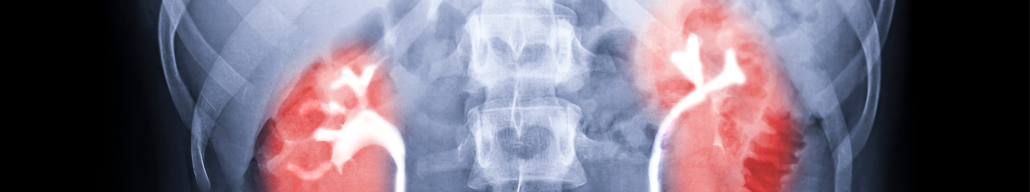

Сотрудники Института химии твердого тела УрО РАН и УрФУ разработали новые гелевые рентгеноконтрастные агенты (РКА) на основе неорганических соединений (танталаты) – сообщает пресс-служба УрФУ1. Они не растворяются в воде, безопасны для пациентов и не вызывают побочных эффектов. Описание агентов и результаты опытов, проведенных in vivo и in vitro, представлены в седьмой главе монографии Challenges and Advances in Chemical Science.

Вместе с сотрудниками Уральского государственного медицинского университета ученые провели доклинические исследования новых РКА. Гелевые рентгеноконтрастные агенты они исследовали при контрастировании различных полых органов лабораторных животных. Агенты показали высокую разрешающую способность при диагностике печеночного дерева и желчного пузыря, а также при диагностике внутриполостных образований в протоках и желчном пузыре, при исследовании желудка, двенадцатиперстной кишки, мочевого пузыря. В результате установили, что новые рентгеноконтрастные вещества безопасны.